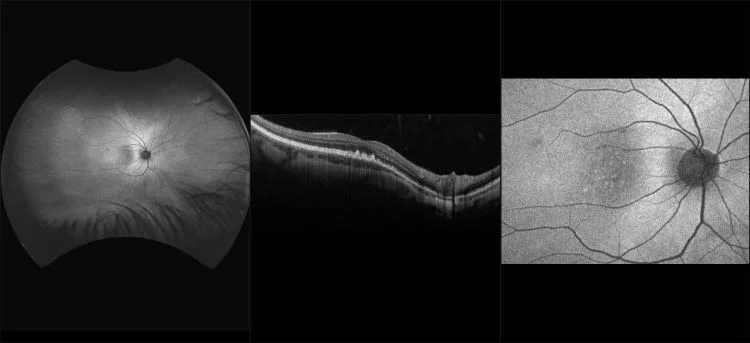

This material is designed as a searchable reference resource to support clinical decision-making. The information contained here should be used as general guidance when viewing optomap and OCT images from Optos devices. The differential diagnosis should be made under the direction of the responsible physician. These images were taken on the latest ultra-widefield optomap devices.

optomap Recognizing Pathology is searchable by pathology and/or optomap image modality. You may search by multiples of each selection. Each individual case is represented by the accompanying thumbnail image. Most cases include several different optomap image modalities. To view a full description of the case, please click on the thumbnail. Each image in the case will be made available through our OptosAdvance software which provides multi-dimensional visualization of digital images to aid in the analysis of anatomy and pathology. Support and pathology definitions can be found by selecting one of the buttons, above. Should you have questions, please complete the form below.